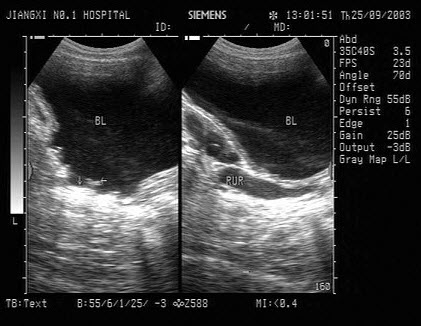

97、单项选择题

男性,有前列腺增生病史,膀胱出现如图的超声表现,最可能的诊断为()

A.膀胱血块

B.膀胱肿瘤

C.膀胱憩室

D.膀胱小梁小房形成

E.慢性膀胱炎